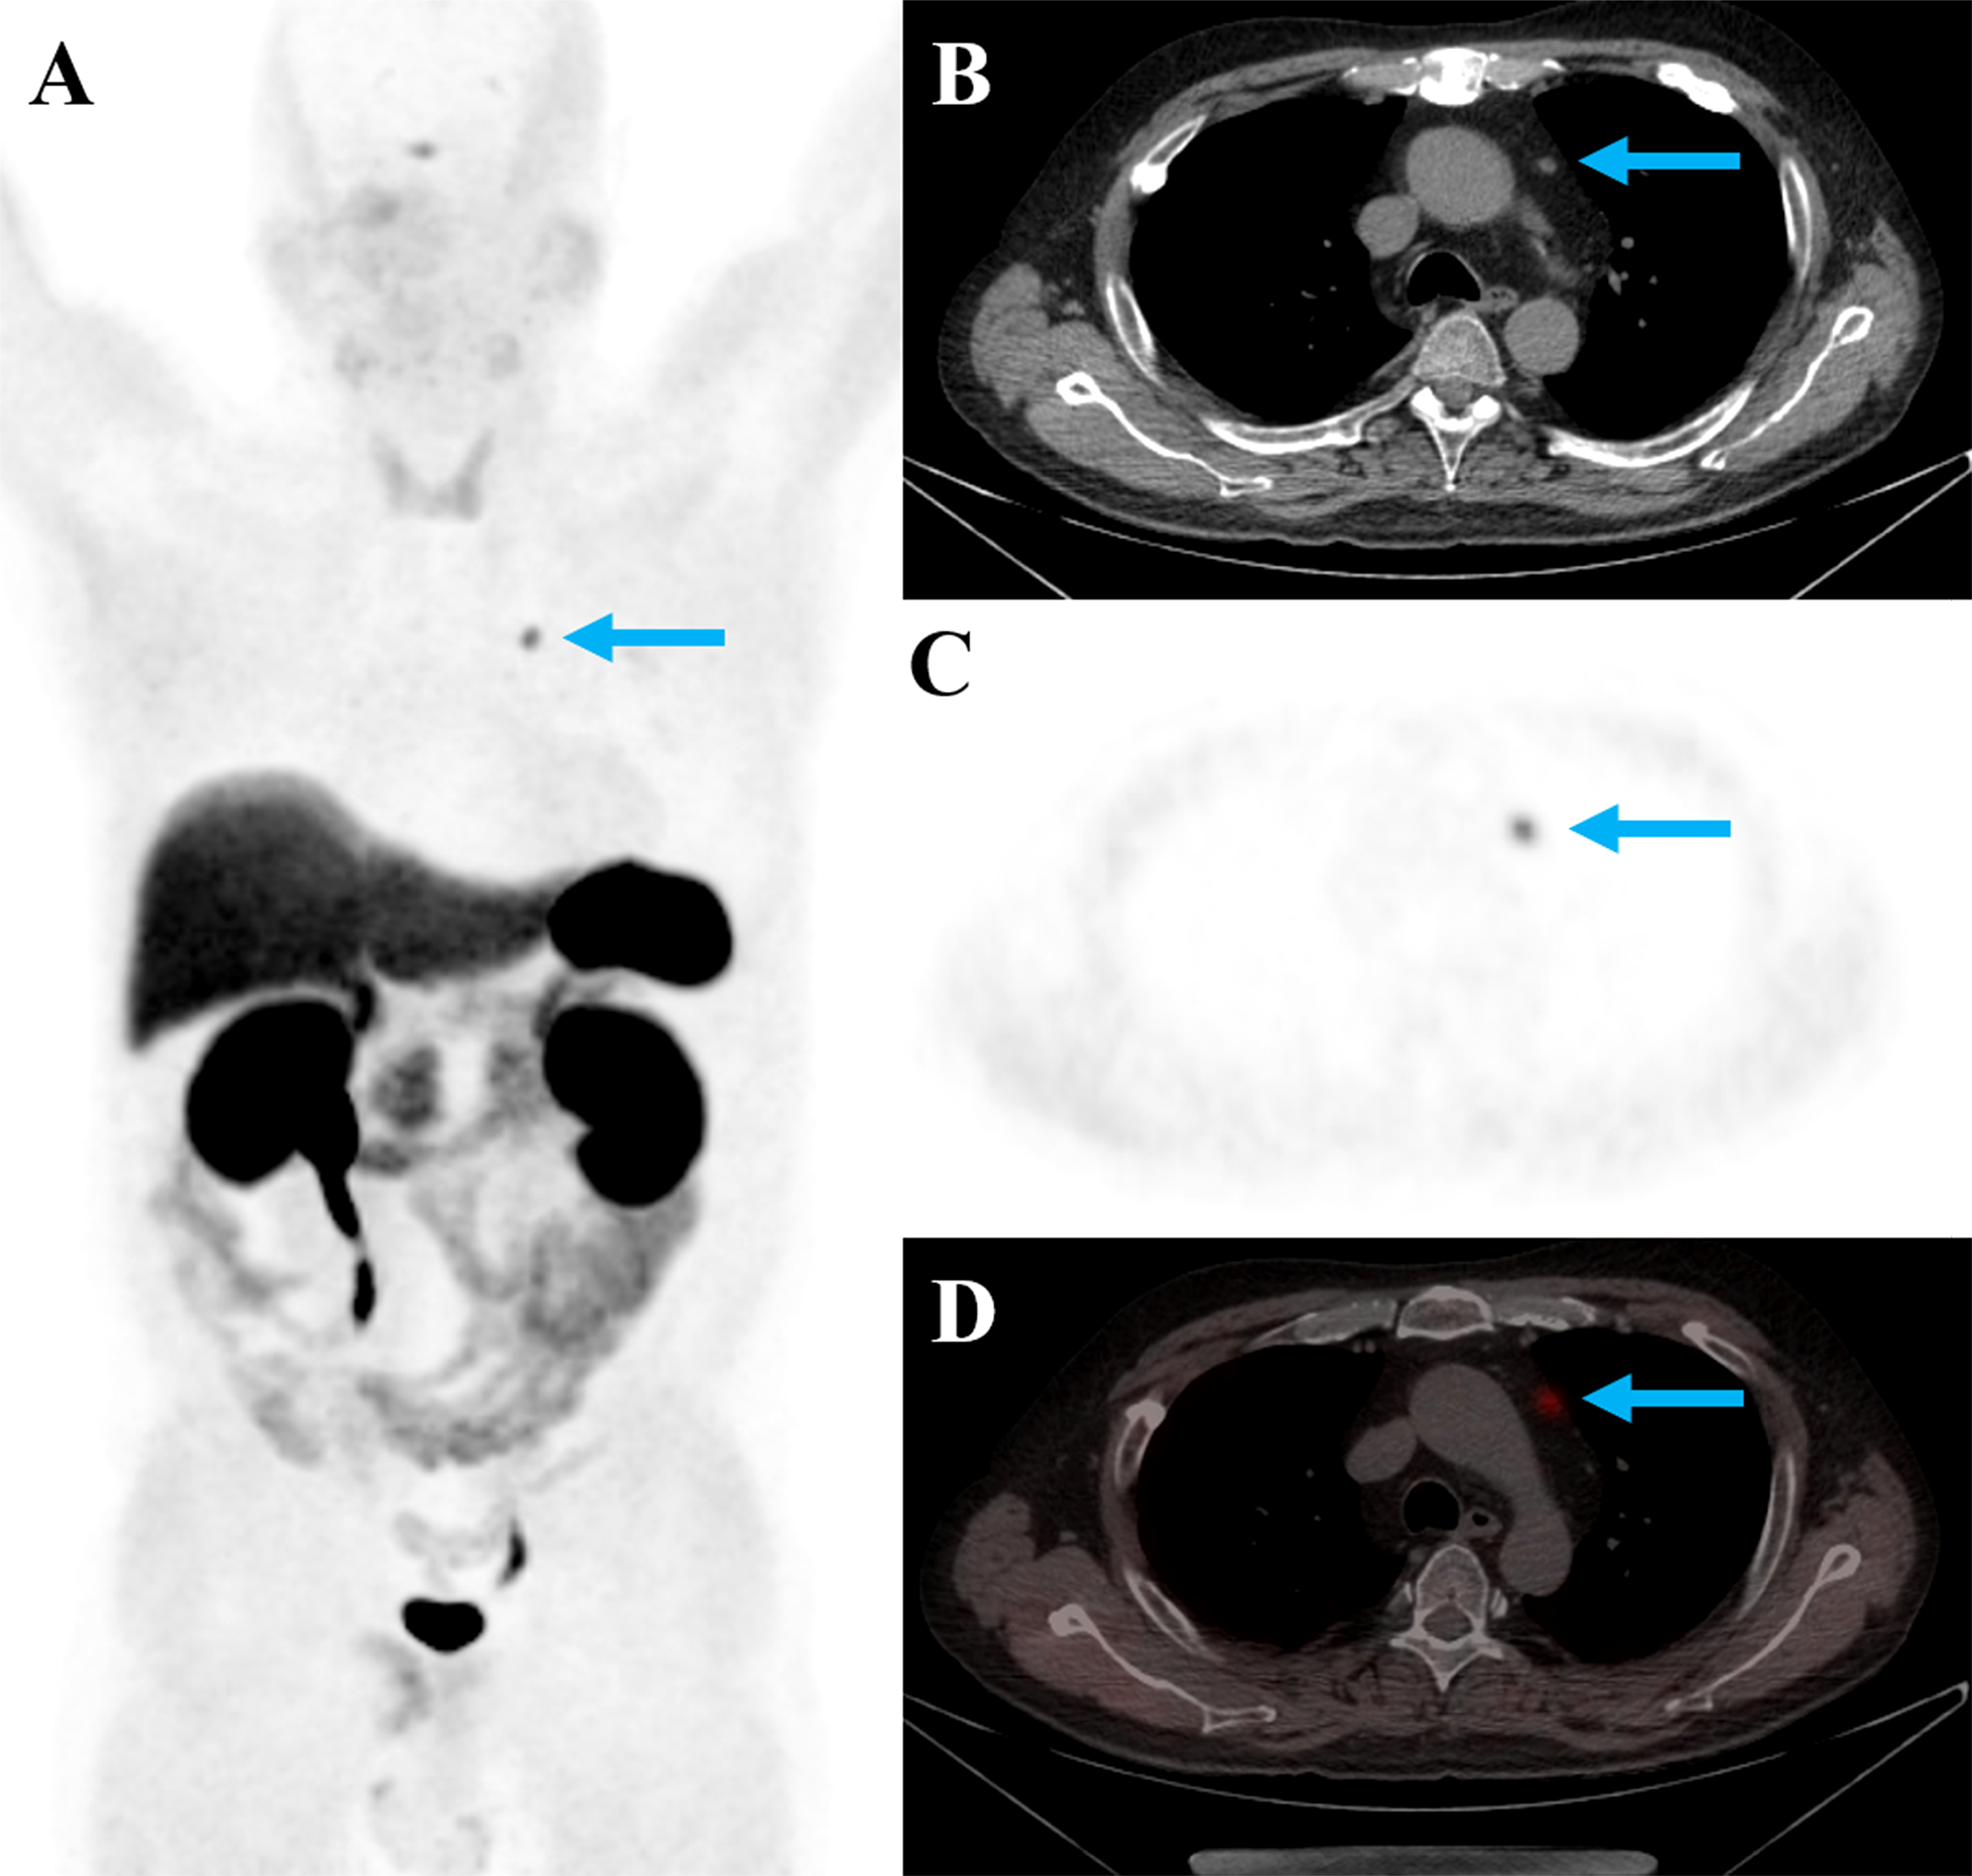

Figure 1

A 53-year-old man with EAS showed positive 68Ga-DOTATATE uptake in the thymic nodule (A–D, blue arrows; tumor SUVmax: 5.2; tumor size: 0.5cm). The nodule was surgically resected, and was pathologically confirmed to be thymic neuroendocrine tumor (G1, Ki-67 index, 1%).